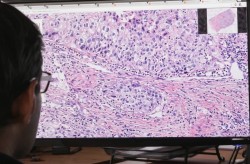

Royal Philips и компания PathAI, разработчик технологии искусственного интеллекта для диагностики патологий, объявили о сотрудничестве с целью повышения точности визуализации рака и других заболеваний. Партнерство направлено на создание решения для глубинного анализа больших массивов медицинских данных с применением технологий машинного обучения и искусственного интеллекта. На начальном этапе сотрудничества специалисты Philips и PathAI будут заниматься разработкой приложений, которые позволят автоматически находить и оценивать пораженные раковыми клетками ткани молочной железы.

С помощью специальных алгоритмов, которые позволяют анализировать большие массивы данных и автоматически определять сходства, врачи смогут ставить более точные диагнозы. Philips уже внедряет технологии глубинного обучения в свои ИТ-решения для визуализации медицинских данных Illumeo и IntelliSpace Portal 9.0. В скором времени компьютерные системы смогут изучать и анализировать тысячи оцифрованных изображений опухолевых тканей и других пациентских данных.